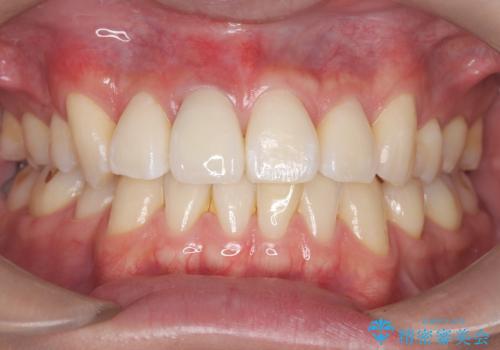

【オールセラミッククラウン】前歯の見た目が気になる!

- 前歯の見た目が気になるを主訴に来院された患者様です。

根管の中が空洞のままで被せ物と歯のきわも合っておらず適合が悪い状態でした。根尖部付近にはパーフォレーションリペア修復の痕がありました。バイオシーシーラーを使用しシングルポイント法で充填しました。空洞があると細菌が増える環境になってしまうので、根管治療からやり直し、緊密に充填しました。被せ物の見た目も大変満足していただけました。